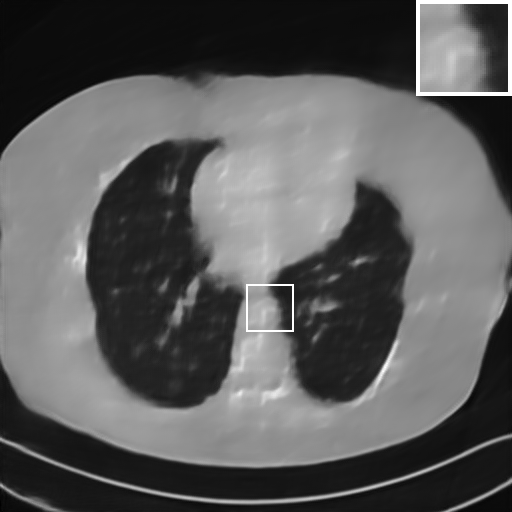

Fig. 4 presents the reconstruction results and residual images obtained by different methods for limited-angle reconstruction. As can be seen, the learning-based methods outperform the direct method and TV model, which exhibit serious artifacts in the missing angle region. Although the denoiser introduced by the FBP-Unet can somehow deal with the noises, the result still presents obvious artifacts. Compared to the SIPID, PD-net and FSR-nets, our LRIP-net1/2 can better preserve the image details and edges with less information left in the residual images. Thus, both the quantitative and qualitative results confirm that the low-to-high double-resolution strategy can improve the reconstruction accuracy for the limited-angle reconstruction problem.

We observe that the low-resolution image prior plays an important role in our method. More specifically, we compare the results of our LRIP-net with respect to different low-resolution priors, which are obtained by down-sampling rate of 1/2, 1/4, and 1/8, respectively. As can be seen in Table III, the best reconstruction results are obtained with the image prior reconstructed by the down-sampling rate of for 150∘, 120∘ and 90∘ limited-angle reconstruction. The visual comparison based on different image priors are also provided in Fig. 5, where obviously less artifacts are left in the reconstruction image by LRIP-net1/8. By comparing the running time, it is easy to see that the smaller the low-resolution image prior, the faster the LRIP-net works.

We further increase the noise level contained in the raw data to 10% white Gaussian noises and list the quantitative results in Table IV. It can be observed that the reconstruction performance of the TV model is poor in the case of high-level noises with PSNR dropping by 4 to 5 dB compared to the previous experiments. On the other hand, the performance of the learning-based methods is less sensitive to noises. The SIPID method relying on the sinogram interpolation works better than FBP-Unet. And the deep unrolling methods (i.e., PD-net, IFSR-net, SFSR-net) outperform the traditional iterative algorithm when the scanning range is limited and data is corrupted by noises. Similar to the previous experiments, compared with other deep learning algorithms, our LRIP-nets give the reconstruction results with higher PSNR and SSIM. Moreover, the low-resolution image obtained by the projection data down-sampled with rate 1/8 always gives the best reconstruction results with more than 2 dB PSNR and 0.05 SSIM increments compared to the PD-net. Fig. 6 illustrates the reconstructed images from different methodologies with scanning angular range of and 10% Gaussian noises. It can be seen that the both TV model and the FBP-Unet suffers from significant artifacts, which present distortions in the angular range of the missing scan. Other learning-based methods provides better visual qualities than FBP-Unet, and our LRIP-net1/8 still gives the best reconstruction result with correct boundaries and fine structures.

Fig. 7 manifests the reconstruction results of these methods with scanning angular of . It can be seen that both FBP and FBP-Unet produce serious artifacts within the range of missing angles. The TV model performs well in removing Poisson noises, but it can not handle the artifacts very well. Similarly, there left obvious artifacts on boundaries and different degrees of missing in visceral tissues of the reconstruction images obtained by the SIPID, PD-net and FSR-net. The visceral tissue and boundaries of our LRIP-net reconstructions are more intact and smoother, especially for the LRIP-net1/8 which gives the ideal boundaries. The observation becomes even apparent if we look at the zoom-in regions, where the LRIP-nets can produce results with fine structures. Therefore, we conclude that the low-resolution image prior can effectively improve the qualities of the limited-angle CT reconstruction.